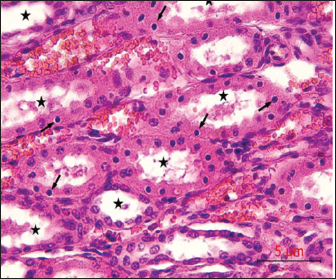

Post-mortem examination resultsPost-mortem examinations of the dead horses infected with M. haemofelis revealed signs of overall emaciation in the affected animals, paleness of internal organs (Fig. 5), and prominent splenomegaly. The liver, kidneys were enlarged; however, the heart showed white patches. Moreover, histopathological changes were characterized by different histopathological changes of eosinophilic degeneration of cardiac muscle fibers, accompanied by atrophy in some fibers, with bleeding between fibers, besides atrophic glomeruli, accompanied with the dilatation of renal tubules in the kidneys, as well as marked reduction in the proportion of white pulp of splenic tissue and degenerative changes in the cytoplasm of hepatocytes, accompanied by nuclear alterations characterized by loss of chromatin content in the hepatic tissue (Figs. 6–9).

Fig. 7. Histological section of the kidney showing dilatation of renal tubular lumina (asterisk), with karyopyknosis of the lining epithelial cells (arrows), H&E,40x. Scale bar=5µm.